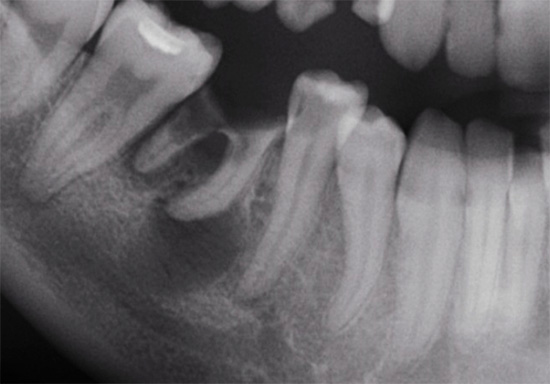

Além disso, métodos de pesquisa radiológica são frequentemente usados para diagnosticar cárie radicular. Eles são ideais para as formas iniciais de cárie radicular, mesmo quando não há cavidade cariada. Nesse caso, usado com mais frequência:

- Roorgenograma de asa de mordida;

- Método de radiografia paralela;

- Orthopantomogram.

A foto mostra um exemplo de raio-x com uma patologia claramente visível na raiz do dente: